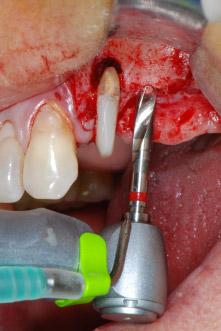

Les lits implantaires ont été préparés sur les sites 25 et 26 à l'aide d'instruments rotatifs, utilisés dans un contre-angle avec un rapport de transmission 20:1 avec un nouveau moteur d'implantologie puissant (Implantmed, W&H) (Fig. 8).

Pour sa précision et sa douceur, le débridement parodontal et l'apicectomie sur le site 24 ont été effectués à l'aide d'un unit piézoélectrique (Fig. 19). Pour ne pas risquer de perdre la dent, un nettoyage soigneux a été nécessaire, mais sans exercer une pression trop forte. Le dispositif a également été utile pour débrider l'os sur le site de l'intervention, une opération qui fonctionne très bien étant donné l'effet de cavitation et les caractéristiques de découpe spécifiques de la technologie.

Le lit implantaire a été préparé à l'aide d'un nouveau moteur d'implantologie (Fig. 20), en combinaison avec un contre-angle spécialement conçu pour la chirurgie orale et l'implantologie.

Grâce à un rapport de transmission de 20:1, ainsi qu'au couple élevé du moteur d'implantologie (jusqu'à 6,2 Ncm), la préparation, l'insertion de l'implant et le taraudage s'effectuent à petite vitesse. La préparation finale jusqu'à la membrane sinusienne a été encore une fois réalisée avec l'unit piézoélectrique et un instrument arrondi recouvert de diamant.